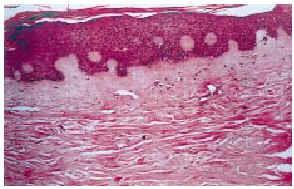

FIG. 5.--Piel con hiperqueratosis, acantosis y fibrosis dérmica.

El estrato córneo mostraba en el 76,5% de los casos un grado variable de hiperqueratosis. El grosor epidérmico era normal en el 45% de las biopsias, atrófico en el 52,9% y aumentado en el 5,8%. Se observó una ligera degeneración hidrópica de la capa basal en el 76,5% de las muestras. En un 17,5% los queratinocitos sufrían ciertos cambios, la mayoría de las veces estaban aumentados de tamaño, con un gran núcleo de aspecto vacuolado y un nucléolo prominente, e incluso en algunos casos observamos queratinocitos binucleados o multinucleados con pérdida de polaridad. En zona suprabasal se reconocían ocasionalmente mitosis, que en algunos casos eran atípicas. Se encontraron células disqueratósicas en un 55% de los casos, así como una hiperpigmentación de la capa basal en el 70,6%. Los melanocitos mostraban un aumento de su tamaño en un 84,3% de las muestras y en un 35% eran además atípicos.

En el 96% de las biopsias a nivel de dermis papilar y porción superior de dermis reticular se observaban luces vasculares dilatadas, con células endoteliales prominentes y núcleo hipercromático en el 27,1% de las mismas. Numerosos melanófagos (80%), células fusiformes grandes de apariencia fibroblástica (63,3%), algunas de ellas estrelladas y en un caso con marcada atipia, edema (41,7%), fibrosis dérmica (36,7%) y un ligero infiltrado linfocitario (63,3%) fueron los otros hallazgos más destacados. En algún caso aislado encontramos espongiosis, infiltrados de eosinófilos o necrosis fibrinoide vascular. Todos estos cambios histológicos no estaban presentes en las biopsias diagnósticas de MF previas al tratamiento con BCNU tópica.

El patrón de dermatitis de la interfase con alteraciones de la maduración se caracteriza por degeneración hidrópica de la capa basal, células disqueratósicas y grandes queratinocitos atípicos con alteraciones más o menos marcadas de la maduración. El estrato córneo frecuentemente muestra una hiperqueratosis compacta y la epidermis presenta una atrofia cuyo grado depende de la intensidad de la reacción. En la dermis destacan los espacios vasculares dilatados y la presencia de «fibroblastos» estrellados (8).

Como hemos detallado antes en el apartado de resultados, la mayoría de nuestras biopsias mostraban los cambios típicos que caracterizan el patrón de interfase. Los cambios más frecuentes en epidermis fueron la hiperqueratosis, degeneración hidrópica de la capa basal, hiperpigmentación y melanocitos aumentados de tamaño, todos ellos en un porcentaje superior al 70%. Otros datos epidérmicos con una frecuencia superior al 50% fueron la atrofia epidérmica y la disqueratosis más o menos marcada. Por otro lado, en dermis destacaba la presencia de luces vasculares marcadamente dilatadas en casi todos los casos, así como numerosos melanófagos y células intersticiales fusiformes aumentadas de tamaño y en ocasiones estrelladas.